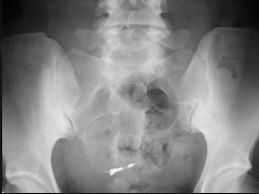

问题 女,45岁,骶髂部疼痛3个月余,请结合影像图像,选择最可能的诊断 ( )

选项 A、骶髂骨骨囊肿 B、骶髂骨骨脓肿 C、骶髂关节结核 D、骶髂关节炎 E、骶髂关节骨折

答案 D